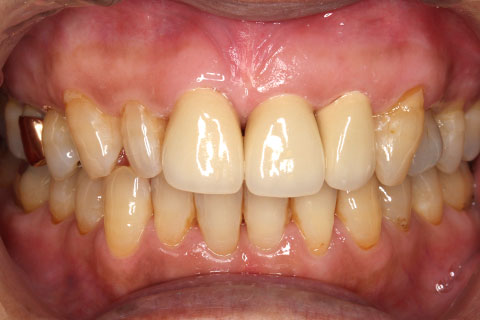

オールセラミックの症例2

- 年齢・性別

- 45歳男性

- 治療期間

- 2ヶ月

- 抜歯

- なし

- 治療費

- 70.4万円

- 備考

- 前歯8本の歯列不正によるセラミック治療

- 治療内容

- 歯質を削除し、セラミック冠をセメント合着

- 施術の副作用(リスク)

- 知覚過敏、歯髄炎、荷重負担